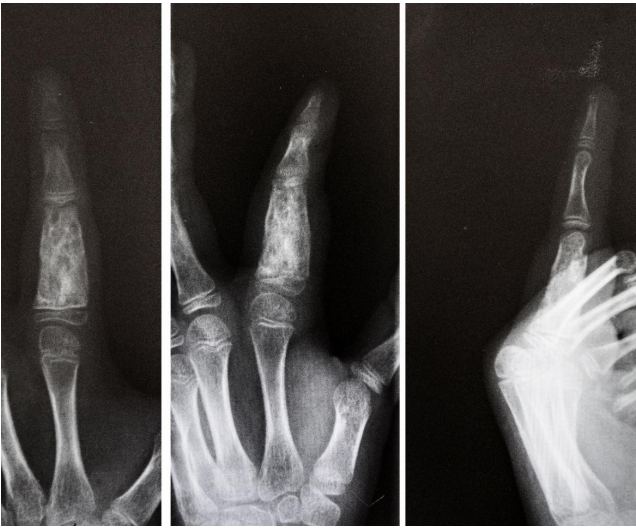

In 2013 Monacelli G, Rizzo MI and Monarca C8 reported a diagnostically challenging case of a young man with GCRG seen in the proximal and middle phalanges of the left middle finger, radiography of the hand showed expansive and lucent lytic lesions with circumferential cortical destruction. He underwent en-bloc resection and reconstruction. Diagnosis was confirmed by Histology

The most common preoperative radiographic diagnosis has been enchondroma, GCT and Aneurysmal bone cyst (ABC). While the location and the expansile nature of the lesion are compatible with enchondroma, GCRG does not exhibit calcification of the matrix. Moreover, the demarcation between abnormal and normal bone is less well defined than in typical enchondroma. ABC is rarely located in the small bones of the hands and feet. Unlike ABC, the majority of the lesions in GCRG occur after closure of the epiphyseal plate.

GCT is the most difficult to distinguish from GCRG; it affects the same age group as GCRG and has similar radiographic signs, except, it is typically more aggressive. Wold LE and Swee RG and colleagues 9, 10 also noted that the clinical and radiologic features did not distinguish between the 2 entities, and a history of trauma was inconsistent.

Radiographs of GCRG usually show a lytic, expansile lesion in one of the phalanges or metacarpals with no evidence of cortical invasion or periosteal reaction, but aggressive variants have been described.